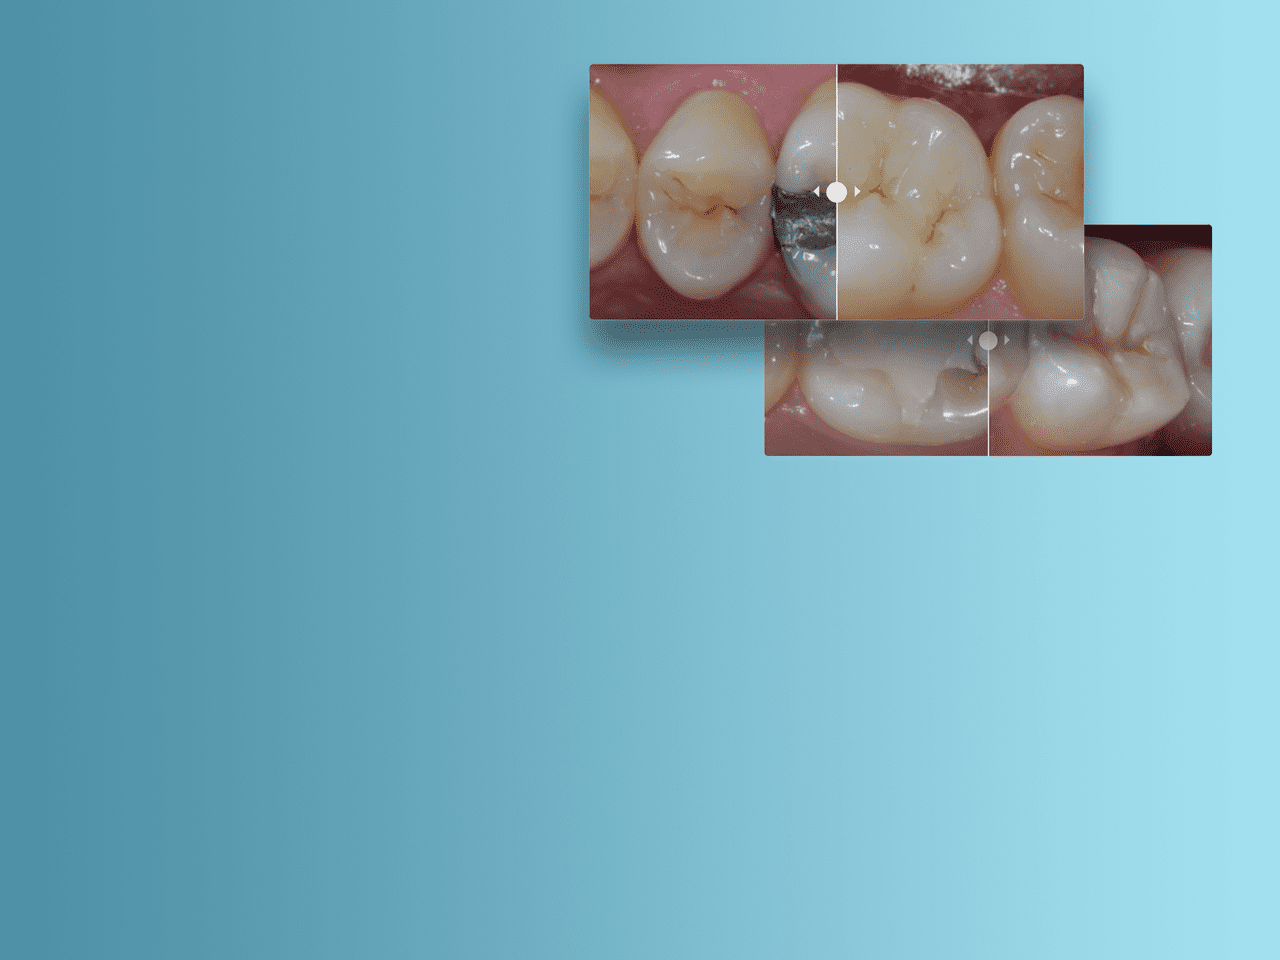

Image :

Avant : restauration postérieure à l’aide de la teinte A2 du composite de restauration Spectra ST (Source : Dr A. Ferrando)

Après : remplacement de l’amalgame par une technique de superposition avancée en utilisant A2 et la teinte blanc décoloré du composite de restauration Spectra ST